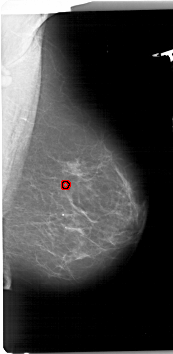

A_1740_1.RIGHT_MLO

RIGHT_MLO LINES 6721 PIXELS_PER_LINE 3286 BITS_PER_PIXEL 12 RESOLUTION 43.5 OVERLAY

FILE: A_1740_1.RIGHT_MLO.OVERLAY

TOTAL_ABNORMALITIES 1

ABNORMALITY 1

LESION_TYPE CALCIFICATION TYPE PLEOMORPHIC DISTRIBUTION CLUSTERED

ASSESSMENT 4

SUBTLETY 2

PATHOLOGY BENIGN

TOTAL_OUTLINES 1

BOUNDARY